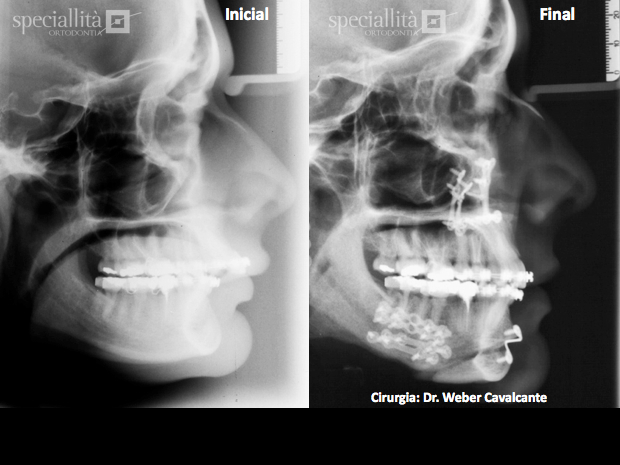

1. Imagens  radiográficas  das  modificações realizadas no perfil facial e nos dentes após cirurgia: abaixamento maxilar, avanço mandibular (video) e recuo do mento